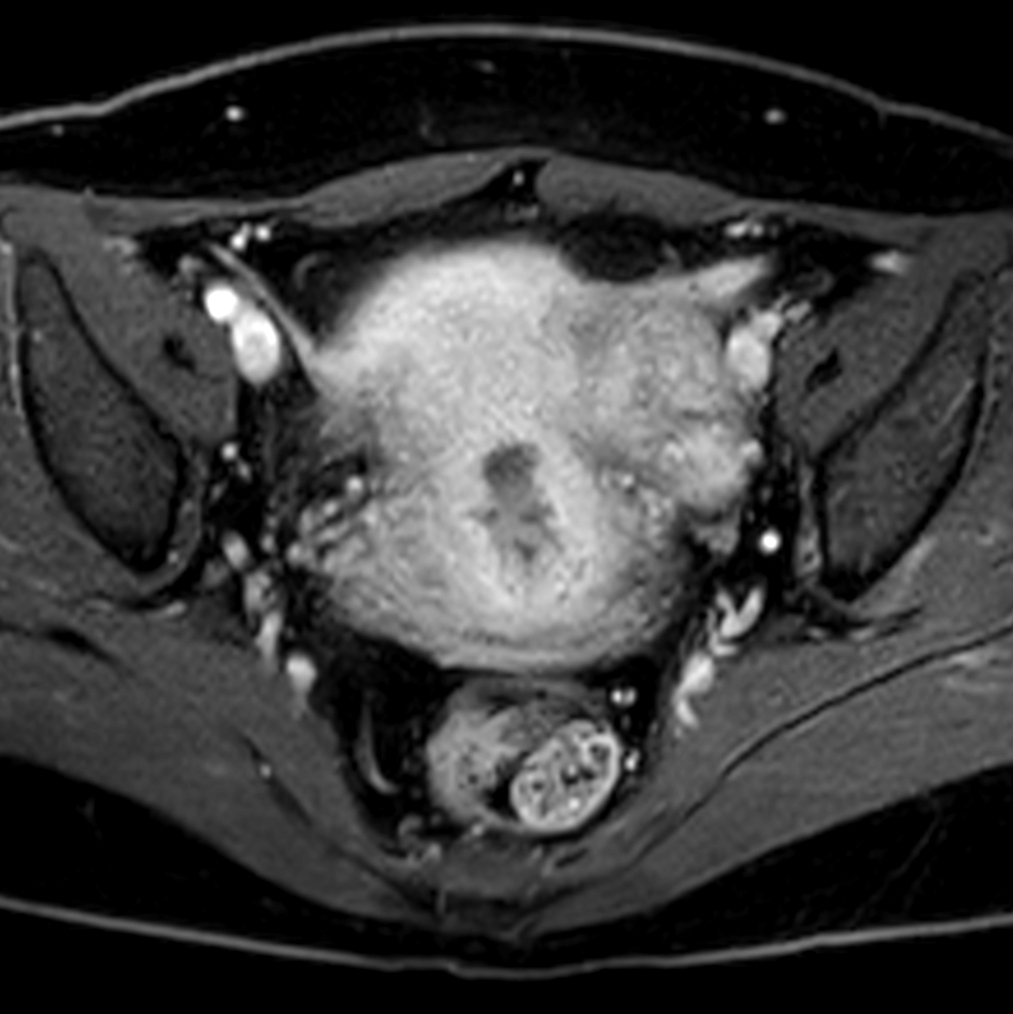

Axial mDIXON XD - T1w FFE plus gado (Water only)